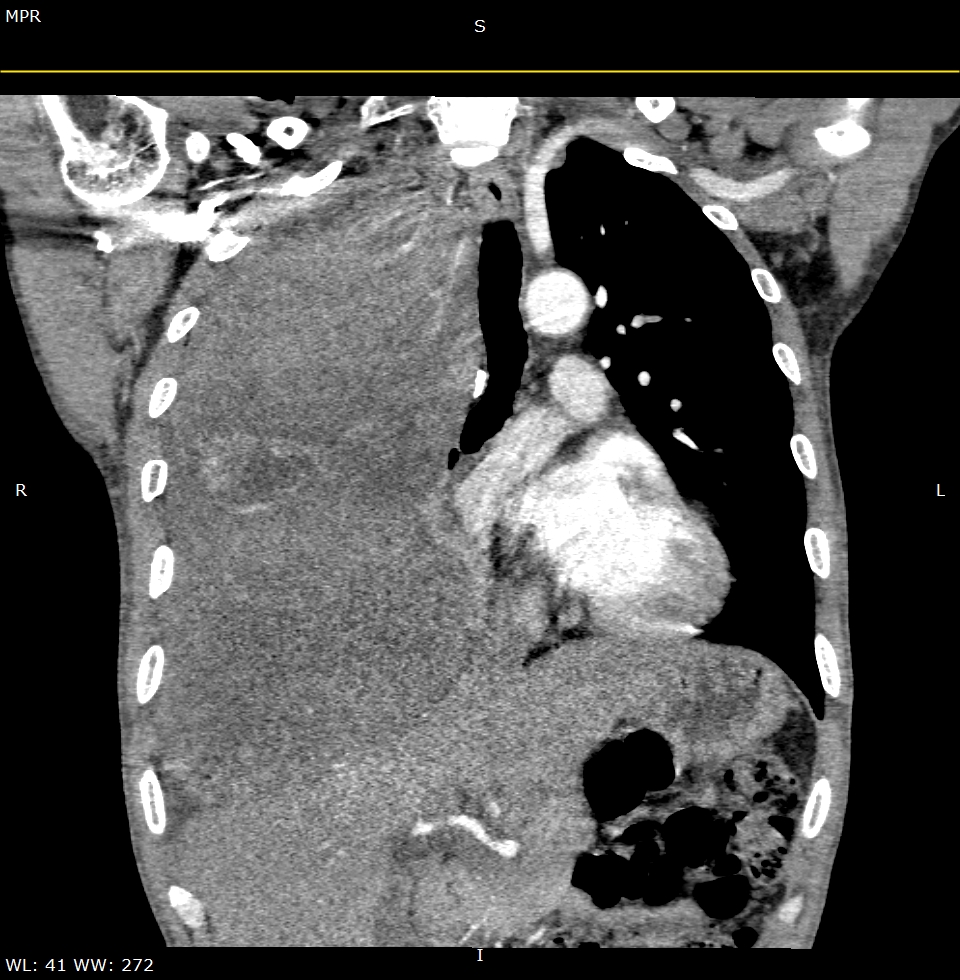

最后,患者经人介绍来到了东北国际医院,胸外科高昕主任在仔细研究了病人资料后表示:“右胸巨大肿瘤;肿瘤向上压迫胸膜顶端,向下压迫膈肌迫使肝肾向腹移位,向内挤压右肺上中叶向肺门内上方,向外挤压左肺下叶向后下方,右侧肺叶因肿瘤压迫呈现肺不张状态;增强CT可见血运似乎来自胸膜顶及肺叶,全身具有典型的肺外症状,如周身关节疼痛,典型的杵状指等,需要手术治疗。但如此罕见的巨大肿瘤,手术难度及风险很大,既然患者及家属多次表态,对我们的技术及能力十分相信,可以收入院完善检查,准备手术治疗”。